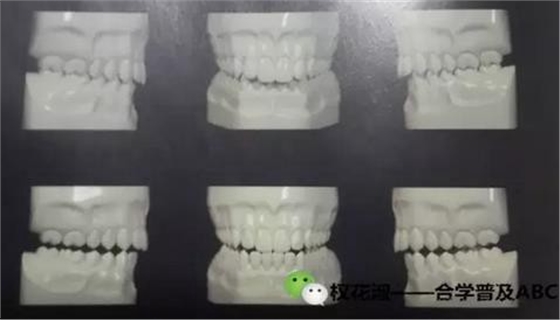

大家看這兩張圖,有什么區(qū)別,做一個比較。

以上給大家是一個靜態(tài)的咬合關(guān)系,只是一個正面的圖,不要在腦海里只想到正面,還要考慮側(cè)面,還要從里側(cè)觀察,當然從舌側(cè)觀察咬合關(guān)系需要在模型上觀察

再看這張圖,這是我的老師的一本專著當中一張插圖,詮釋的是尖牙保護合,我們牙齒的一個動態(tài)的接觸關(guān)系,是一種邊緣運動的咬合關(guān)系,看下圖三個模型,中間是前伸運動時后牙的咬合分離,左側(cè)的是向左側(cè)方運動時只有尖牙接觸,其他牙齒咬合分離,右側(cè)是向右側(cè)方運動時只有尖牙接觸,其他牙齒咬合分離。這是理想狀態(tài)下的咬合關(guān)系,那在非理想狀態(tài)下咬合的側(cè)方運動是怎么的接觸關(guān)系呢。

這三張圖表達的是通常所說的組牙功能,在做側(cè)方運動時除了尖牙以外的牙齒有接觸,(或者尖牙沒有接觸),其他牙也有接觸的多組牙齒接觸的咬合狀態(tài),這種動態(tài)咬合關(guān)系,歸類為非理想的一種動態(tài)咬合關(guān)系。